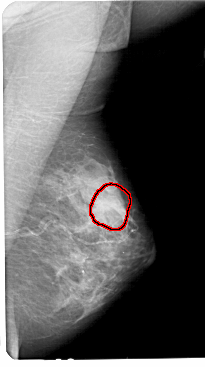

A_1447_1.RIGHT_MLO

RIGHT_MLO LINES 5491 PIXELS_PER_LINE 3061 BITS_PER_PIXEL 12 RESOLUTION 43.5 OVERLAY

FILE: A_1447_1.RIGHT_MLO.OVERLAY

TOTAL_ABNORMALITIES 1

ABNORMALITY 1

LESION_TYPE MASS SHAPE LOBULATED MARGINS OBSCURED

ASSESSMENT 3

SUBTLETY 1

PATHOLOGY BENIGN

TOTAL_OUTLINES 1

BOUNDARY